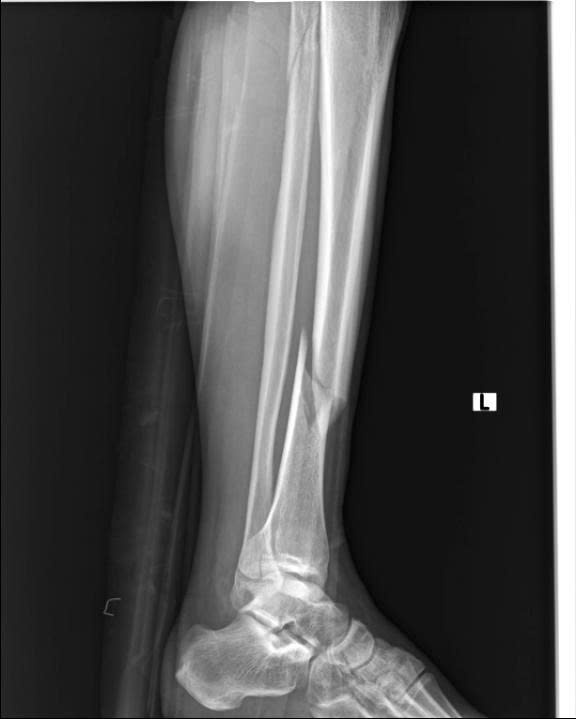

Hình ảnh: Xquang xương trước phẫu thuật

- Hình ảnh X-quang sau mổ cho thấy xương được nắn chỉnh và cố định vững chắc